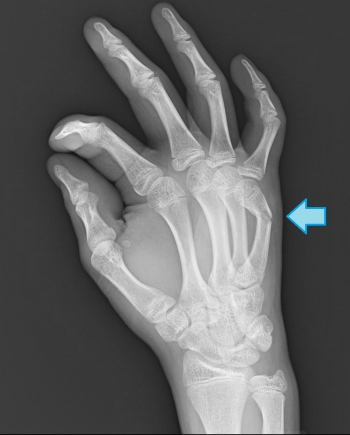

今日、ご紹介するのは、手指骨骨折の分類の詳細についてご紹介していきたいと思います。

手指骨折の分類

基節骨骨折

①骨幹部骨折 ②骨頭・頚部骨折 ③基底部骨折

中節骨

①頚部骨折 ②骨幹部骨折

末節骨骨折

①マレットフィンガー

比較的頻度の高い骨折です。

完全骨折の場合は、しばしば定型的な掌側凸変形になる。

スポーツによる過伸展や過屈曲による損傷が多い。

骨幹部骨折

近位骨片は虫様筋や骨間筋により屈曲、遠位骨片は背側腱膜により掌側凸に転位する。

骨頭・頚部骨折

頻度としては高くないですが見逃されやすく、小児に多い骨折

骨折した骨頭部は、骨折端を掌側に向けて90°回転し、側副靭帯により絞扼されて整復が困難。

基底部骨折

掌側凸の変形を呈す。

小児には骨端線離開を見ることもある。

中節骨骨折

基節骨と比べると頻度は低い。

頚部骨折、骨幹部骨折、基底部骨折に分けられる。

皆さん、突き指は一度はしたことがあると思いますが、そこには骨折もしている可能性があります。

早期にレントゲンを撮りましょうね